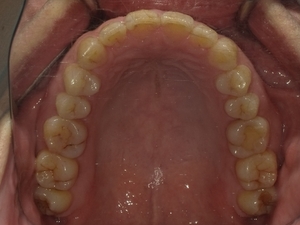

○ご相談内容:下の歯のがたつき○矯正の種類:マウスピース型矯正「クリアコレクト」○治療期間:10週間○治療費用:66万円(税込)